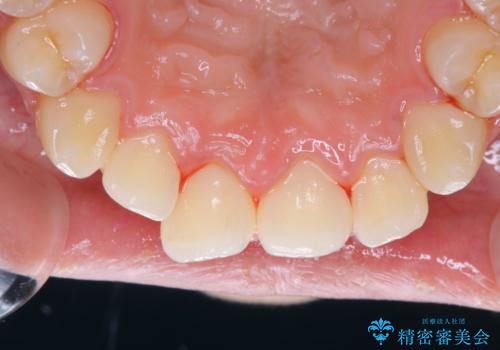

- しばらく歯科でのメンテナンスを受けていないため、歯磨きのチェックとクリーニング希望とのことで来院されました。

染め出しをしてのブラッシング指導とPMTCを行いました。